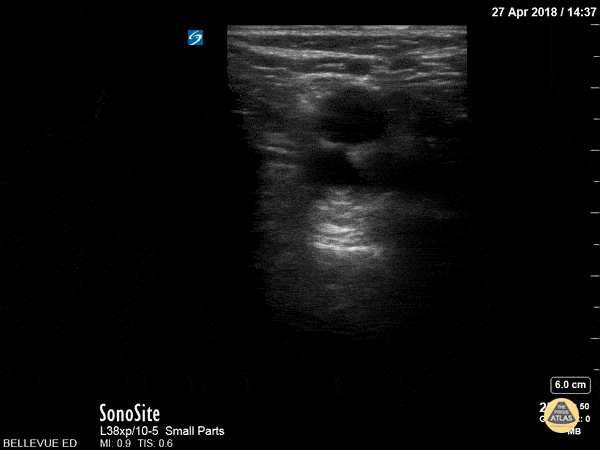

This clip demonstrates compression of the popliteal vein moving distally from the popliteal fossa down the calf as is often done to assess for DVT. The non-compressible vessel deep and medial to the popliteal vein is the popliteal artery. Hannah Kopinksi and Dr. Lindsay Davis - NYU Emergency Medicine